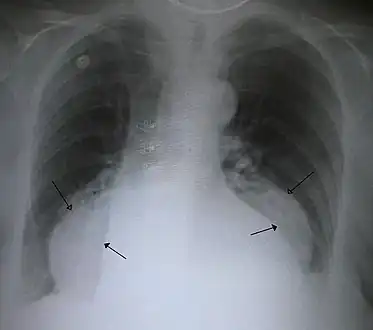

- A large hiatal hernia on chest X-ray marked by open arrows in contrast to the heart borders marked by closed arrows

This hiatal hernia is mainly identified by an air-fluid level (labeled with arrows).